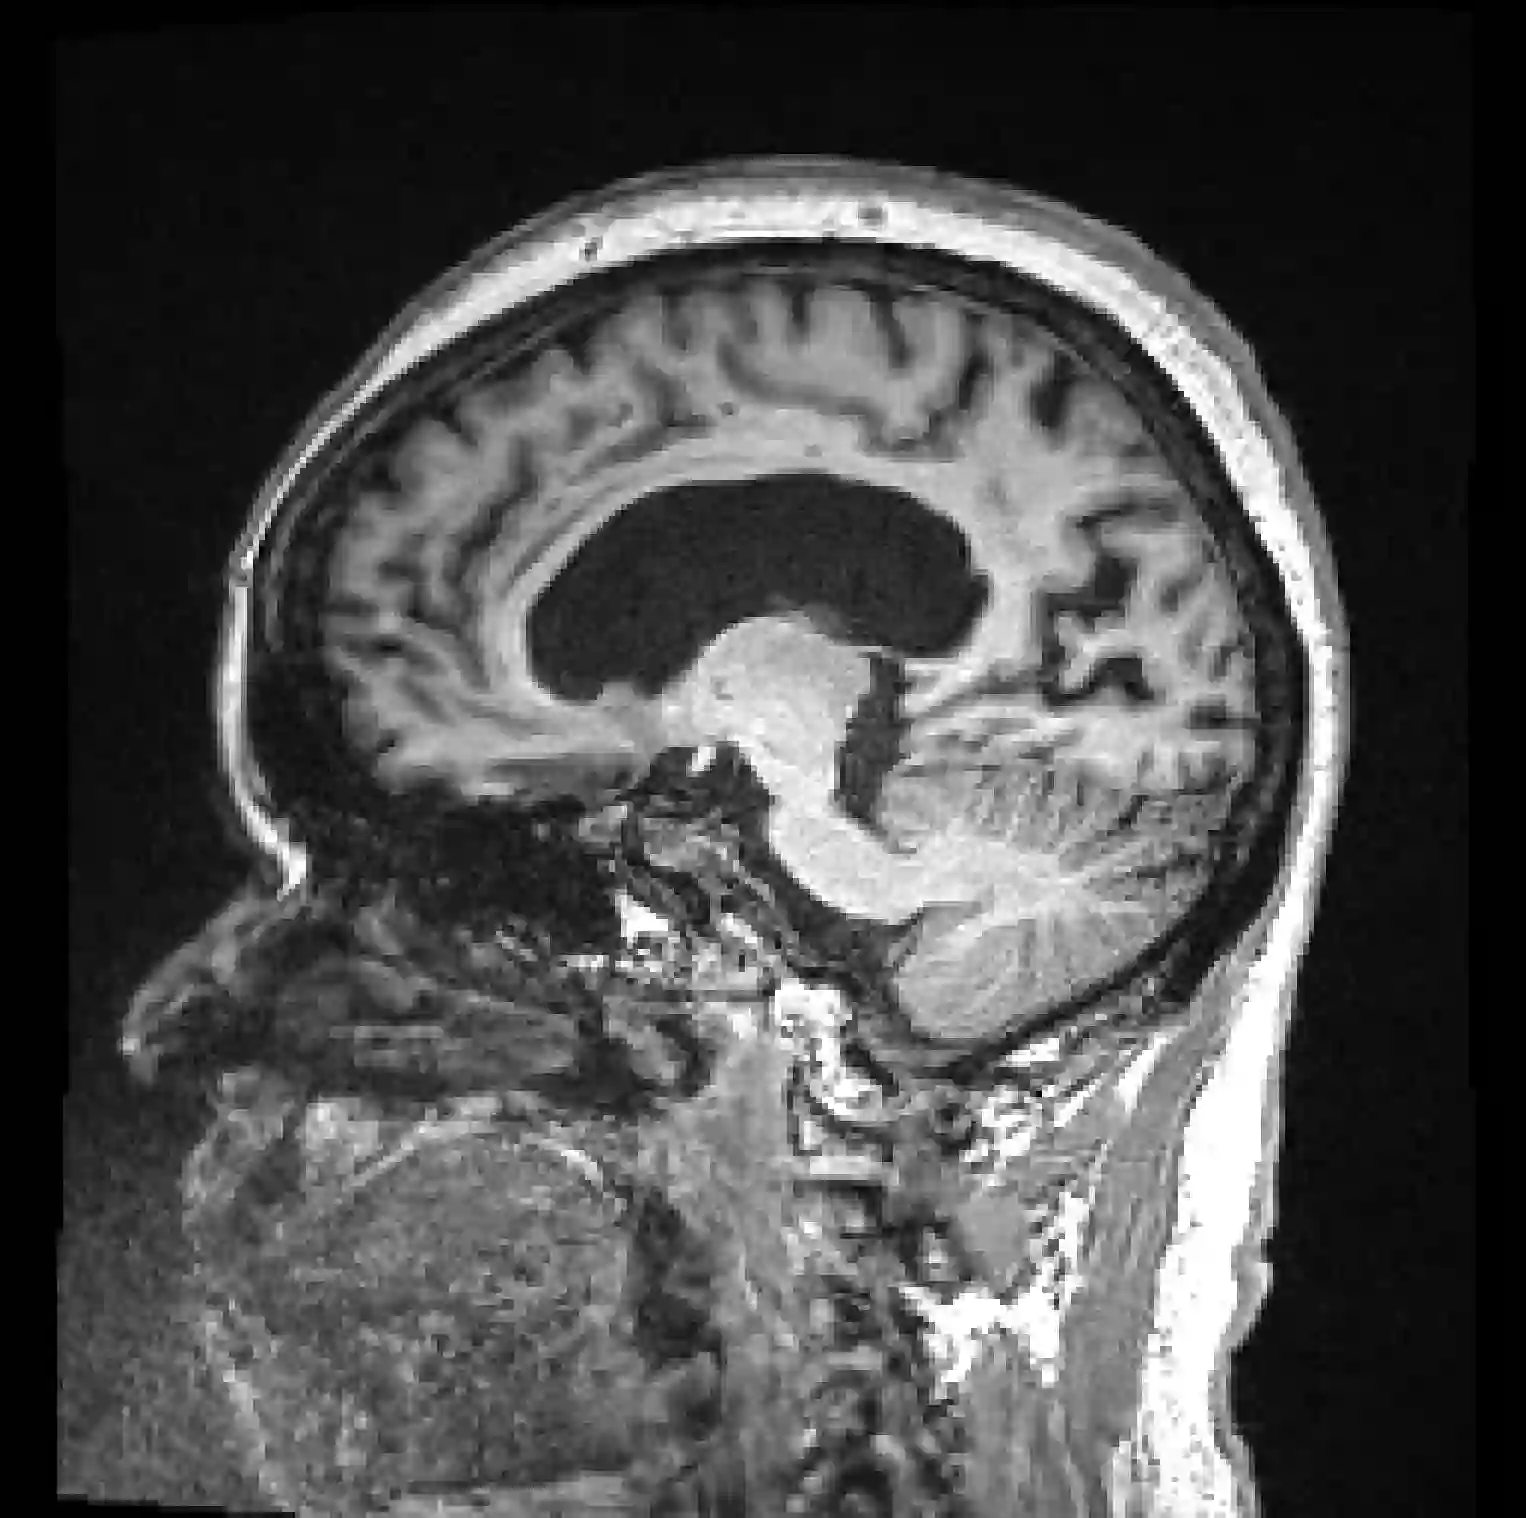

Quality control (QC) of MR images is essential to ensure that downstream analyses such as segmentation can be performed successfully. Currently, QC is predominantly performed visually and subjectively, at significant time and operator cost. We aim to automate the process using a probabilistic network that estimates segmentation uncertainty through a heteroscedastic noise model, providing a measure of task-specific quality. By augmenting training images with k-space artefacts, we propose a novel CNN architecture to decouple sources of uncertainty related to the task and different k-space artefacts in a self-supervised manner. This enables the prediction of separate uncertainties for different types of data degradation. While the uncertainty predictions reflect the presence and severity of artefacts, the network provides more robust and generalisable segmentation predictions given the quality of the data. We show that models trained with artefact augmentation provide informative measures of uncertainty on both simulated artefacts and problematic real-world images identified by human raters, both qualitatively and quantitatively in the form of error bars on volume measurements. Relating artefact uncertainty to segmentation Dice scores, we observe that our uncertainty predictions provide a better estimate of MRI quality from the point of view of the task (gray matter segmentation) compared to commonly used metrics of quality including signal-to-noise ratio (SNR) and contrast-to-noise ratio (CNR), hence providing a real-time quality metric indicative of segmentation quality.

翻译:MR图像的质量控制(QC)对于确保成功进行分化等下游分析至关重要。目前,QC主要是在视觉和主观上进行,时间和操作员成本都很高。我们的目标是利用一个概率网络使这一过程自动化,通过一个偏振性噪音模型来估计分解不确定性,提供量度任务质量的量度。通过用 k- 空间人工制品来增加培训图像,我们提议一个新的CNN结构,以自我监督的方式分解任务和不同 k- 空间人工制品的不确定性来源。这样可以预测不同类型质量退化的不确定性。虽然不确定性预测反映了工艺品的存在和严重程度,但根据数据质量,网络提供了更可靠和可概括的分解预测。我们显示,经过艺术增强培训的模型提供了模拟工艺品和人类计数者发现的有问题的真实世界图像的不确定性度度,无论是质量和数量上的误标度。将亚精度不确定性与分解DRC的分度联系起来。我们观察到,从分解性预测反映了工艺品的存在和严重性分解率,我们用到比较了比性质量分数质量的比点,包括标准化的比标值的比点。